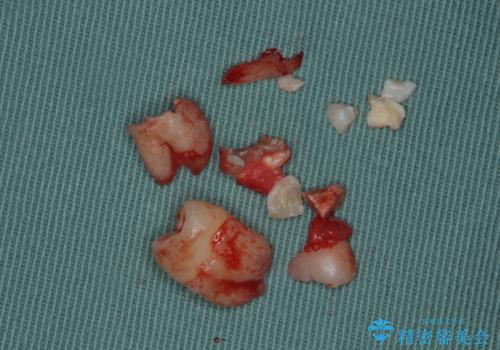

- 右上下親知らずを抜きたいとの事で来院。

レントゲンを確認したとこと完全埋伏歯でした。

CTで神経の位置などを確認し、抜歯術を行いました。

無事抜歯を行うことができました。